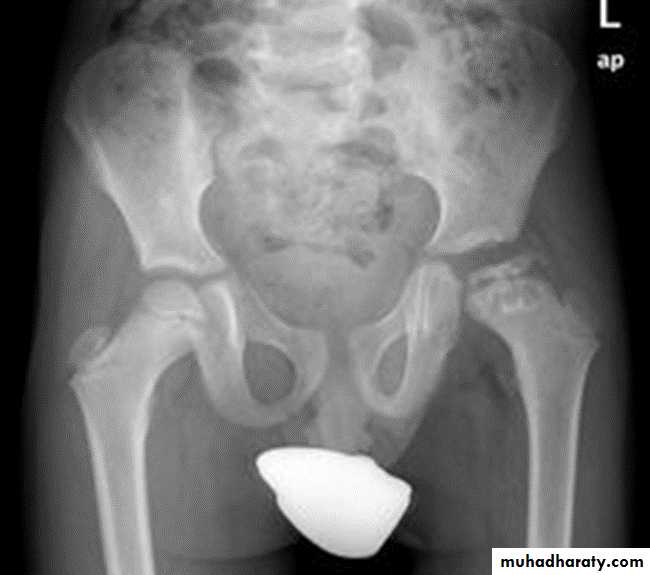

DEVELOPMENTAL DYSFLASIA OF HIP (CONGENITAL DISLOCATION OF THE HIP)

An abnormally lax joint capsule allows the femoral head to fall out of the acetabulum, leading to deformation.

Predisposing factors for the development of CDH are:

* Abnormal ligamentous laxity (effect of estrogen; fema1e:male = 6:l)

* Acetabular dysplasia .

CDH occurs most commonly (70%) in the left hip. Bilateral involvement is seen in 5%.

Radiographic features:

US (commonly used today) at 1-3 months

* Normal femoral head is covered at least 50% by acetabulum , In CDH < 50% of femoral head is covered by acetabulum .

Plain film

At 3-6 months :

By doing special veiw (Von Rosen veiw )by abduction of the thigh 45 degree and internal rotation .

In DDH the lines that drown through the femura will meet in higher level than the normally should at lumbosacral joint .

6 months and later

* AP veiw ( femural epiphysis are visualized ):* Superolateral displacement of proximal femur (disturbed shenton’s line )

* Increase in acetabular angle

* Small capital femoral epiphysis

Femoral head is located lateral to Perkin's line

* Other features that are sometimes present

Abnormal sclerosis of the acetabulum

Shallow acetabulum

Formation of a false acetabulurn